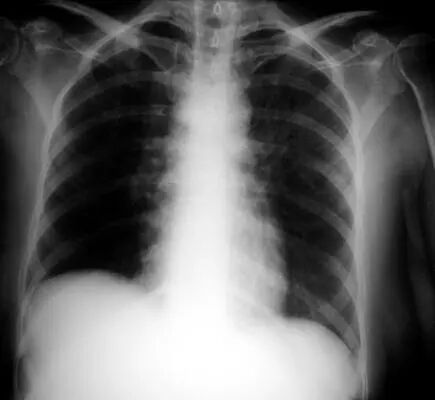

图1.2 细菌性肺炎。双肺下叶肺炎患者影像。